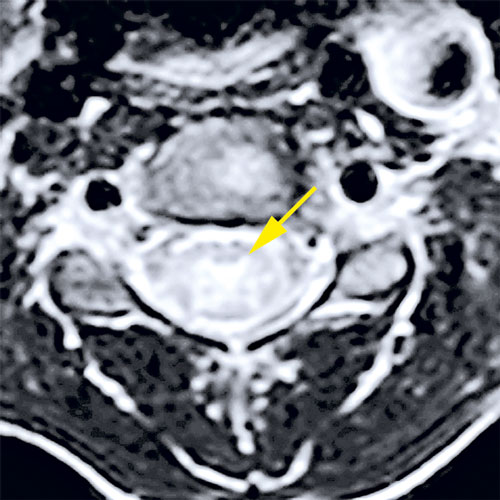

Fall 1. En 9 år gammal flicka sökte på barnakuten efter att ha haft feber i några dagar och vaknat med uttalad svaghet i höger arm. Akut DT-undersökning av hjärna visade normala fynd. Kompletterande MR-undersökning visade signalförändringar i bakre delen av pons och långsträckta signalförändringar i ryggmärgens gråa substans (mer expansiva i halsryggmärgen än i övriga ryggmärgen). Inget patologiskt kontrastmedels­upptag påvisades (Figur 1). MR ingav först misstanke om spinal tumör, men eftergranskning visade en mer tydlig inflammatorisk bild och tumörmisstanken kunde avskrivas. Lumbalpunktion visade lätt pleocytos. Mikrobiologisk utredning i blod och likvor utföll negativ. Prov från feces och nasofarynx togs inte.

Figur 1 (fall 1). Vid initial MR-undersökning visade T2-viktad sekvens expansiva signalförändringar över hela cervikala ryggmärgen (första bilden) jämfört med mer kaudala delar; axialt T2-viktad sekvens i höjd med C4 visade mer expansiv grå substans (andra bilden). T2-viktad FLAIR (fluid attenuated inversion recovery) visade förhöjd signal i bakre delen av pons (tredje bilden). Vid MR-undersökning 10 dagar senare kunde T2-viktad sekvens inte påvisa signalförändringarna i ryggmärgen (fjärde och femte bilden). På T2-viktad FLAIR har signalförändringarna i pons gått i regress (sista bilden).